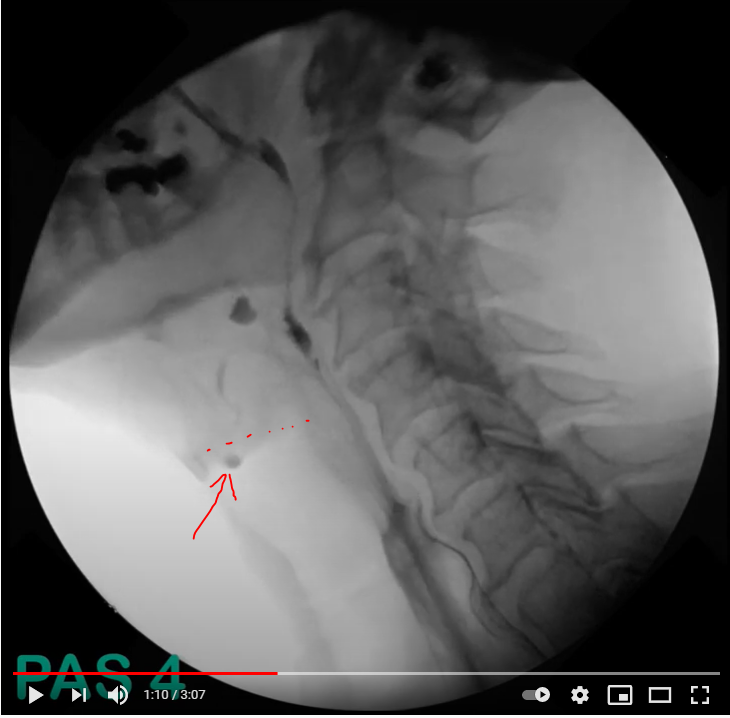

PAS

1. 기도로 조영제 들어가지 않음

2. 기도로 조영제 들어감. 보컬코드 위에만 존재, Residue 남지 않음

3. 보컬코드 위에 조영제 남고, Residue 보임

4. 조영제가 보컬코드에 닿음. 레지듀는 안남음

5. 조영제가 보컬코드에 닿음. 레지듀 남음

6. 조영제가 glottis를(=vocal cord) 통과, subglottic residue는 안 보임

7. 조영제가 glottis를 통과, subglottic residue는 보임, 환자 반응은 있음

8. 조영제가 glottis를 통과, subglottic residue는 보임, 환자 반응은 없음